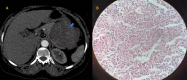

Figure 3

Figure 3. Plain (A) and portal venous phase of contrast-enhanced (B) axial CT scan images show a thick-walled hypodense cystic lesion with tiny focus of calcification at the periphery. On HPE, it was proven to be a case of mucinous cystadenoma of the pancreas

CT: computed tomography; HPE: histopathological examination